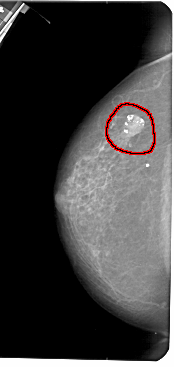

A_1306_1.LEFT_CC

FILE: A_1306_1.LEFT_CC.OVERLAY

TOTAL_ABNORMALITIES 1

ABNORMALITY 1

LESION_TYPE CALCIFICATION TYPE AMORPHOUS DISTRIBUTION N/A

LESION_TYPE MASS SHAPE OVAL MARGINS CIRCUMSCRIBED

ASSESSMENT 2

SUBTLETY 5

PATHOLOGY BENIGN

TOTAL_OUTLINES 1

BOUNDARY